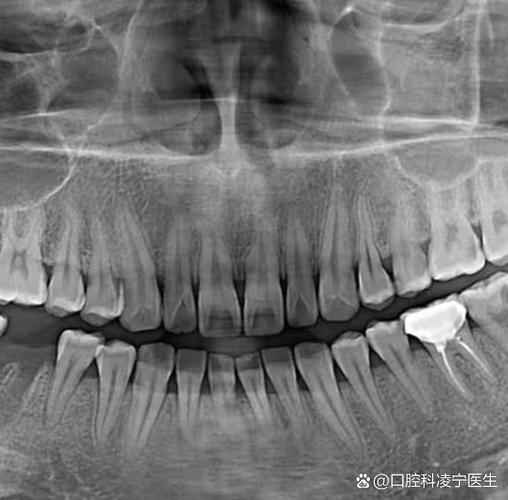

全景片 (曲面断层片 - Panoramic Radiograph, OPG/Panorex):

(图片来源网络,侵删)- 目的: 这是最基础也是最重要的片子之一,它像一张展开的牙齿地图,可以同时显示上下颌所有牙齿(包括埋伏牙、多生牙、缺失牙)、牙根形态、牙槽骨高度和密度、颌骨的轮廓、上下颌牙列的整体关系、以及重要的解剖结构(如上颌窦、下颌神经管)。

- 作用: 诊断牙齿数量异常(多生牙、缺失牙)、牙齿位置异常(埋伏阻生、倾斜)、牙根形态(弯曲、吸收)、牙槽骨健康状况、评估拔牙空间、观察颌骨发育情况等。